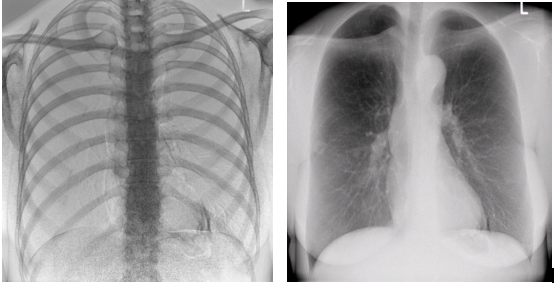

1)大视野无遗漏

17*17英寸的高清像素动态平板探测器,能对胸部、腹部等部位实现大范围全覆盖,动静态之间无感切换。透视检查无须对患者重新定位便可观察到足够大的人体器官组织,避免漏诊误诊。更好地减少了曝光时间,也减少了病人的辐射剂量。

大尺寸动态平板技术,覆盖检查面积范围广,轻松实现胃十二指肠等大面积造影,无需移动即可观看整个动态过程,避免噪点对图像的影响。